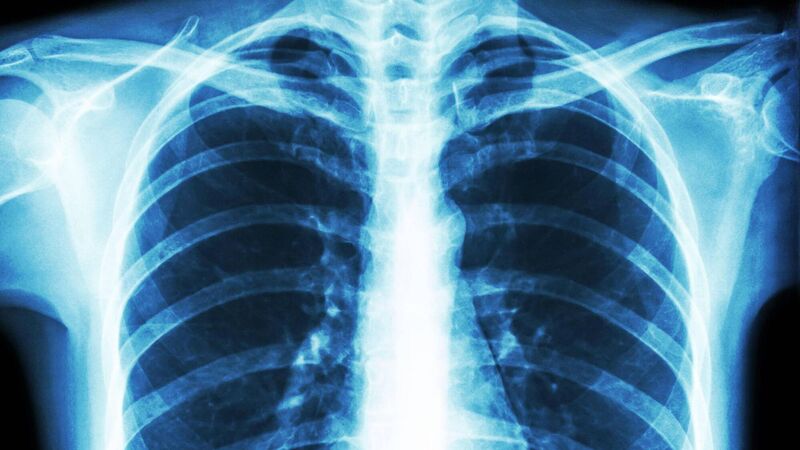

People with lung conditions most at risk from climate change, respiratory experts warn

People with lung conditions are among those most at risk from the changing climate, a group of respiratory experts has said.